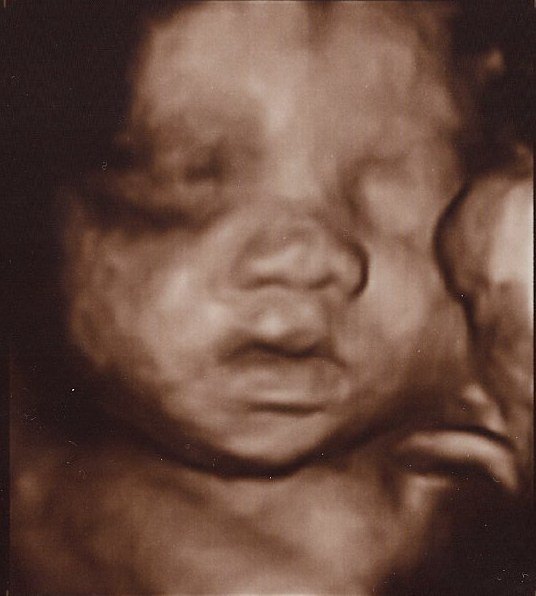

Det er så vildt at være til 3D scanning, det er som om, man er gravid på en helt anden måde bagefter

Ja, virkelig! Det er en hel anden måde at forholde sig til den lille på! Men når man ser billederne synes jeg man tænker "iih hun er stor", men hun er jo i virkeligheden stadig lillebitte. Lidt skægt